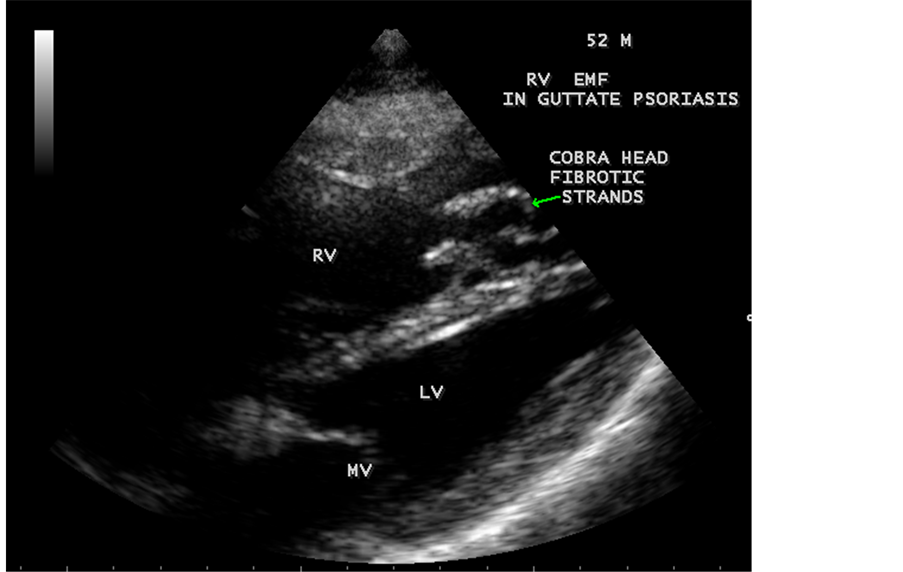

Transthoracic echocardiography revealed strong fibrous strands appearing as “finger like projections” or “cobra-head” appearance in the right ventricular apex due to fibrosis of muscular trabeculae, suggesting right ventricular endomyocardial fibrosis as shown in Figure 3 to Figure 7.

Figure 4. Tilted apical view showing the “cobra-head” appearance of fibrous strands suggesting right ventricular endomyocardial fibrosis in a 52-year-old male with Psoriasis.

enlargement as in Figure 33 are the characteristic features of advanced stage of EMF. The fibrosed muscular trabeculae extending into the cavities from the walls of the chambers in the right ventricle visible as “cobra heads” as in Figure 4 and in pericardial sac as in Figure 29. Aneurysmal right ventricle with scattered areas of fibrosis in the sub tricuspid region and a notch in the right atrium is well seen in a 14-year-old boy as in Figure 43. Right atrial notch is frequently noticed in EMF patients as shown in Figure 42 in a 47-year-old male with left ventricular EMF and moderate pericardial effusion.